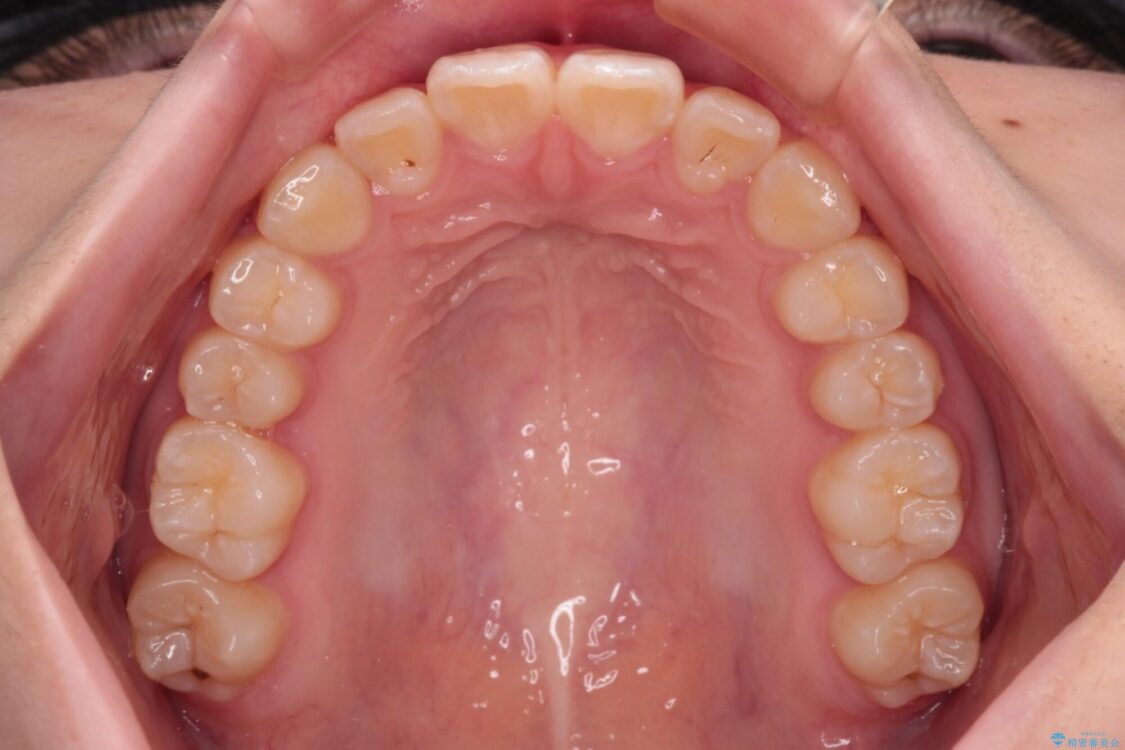

上下前歯のねじれを気にして来院された患者様です。

ワイヤー矯正でもマウスピース矯正でも対応可能でしたが、マウスピース矯正の自己管理が面倒であること、上顎前歯の捻転が著しいことから、ワイヤー矯正での治療を希望されました。

治療前

• インビザラインは使える自信がない ワイヤー装置にて矯正治療 治療前画像